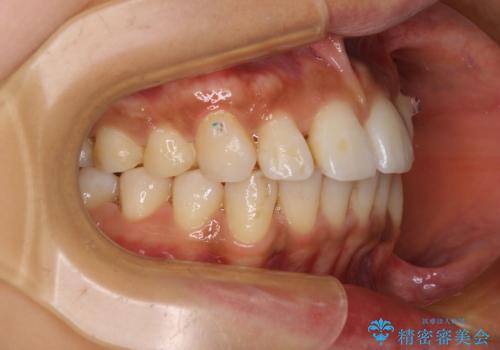

カリエール・ディスタライザーを併用したインビザライン矯正治療

- 全体的な歯列の叢生を気にして来院された患者様です。

奥歯の咬み合わせを見ると、片方は上顎が下顎に対して相対的に前方にある状態でした。

咬み合わせを改善するためには、上顎臼歯を後方に移動させた咬み合わせにする必要があります。

インビザライン単体で改善することも可能ですが、ディープバイトのためインビザライン単体で達成する可能性が低いと考えられたため、カリエール・ディスタライザーという補助装置を併用して、より確実性を上げることとしました。

奥歯の咬み合わせ改善後に、インビザラインにて歯列を整えることとしました。